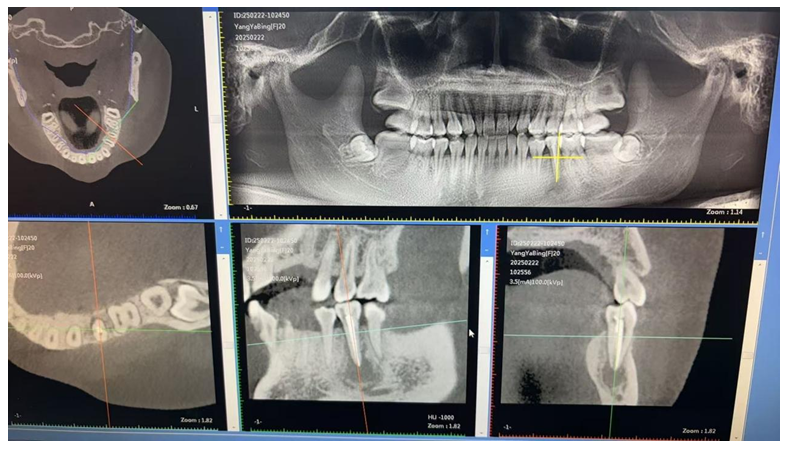

数字化导板技术:通过口腔 CT 扫描获取患者口腔颌骨的精确三维数据,利用计算机辅助设计(CAD)和计算机辅助制造(CAM)技术制作出个性化的手术导板。在牙槽外科手术中,如拔牙、种植牙等,导板可以精确引导手术器械的操作,提高手术的准确性和可预测性,减少手术创伤和并发症,同时缩短手术时间。

自提牙移植技术:是将患者自身的牙齿从一个位置移植到另一个需拔除患牙或缺失牙的位置上,使其在新位置愈合后行使咬合功能,恢复牙列缺损